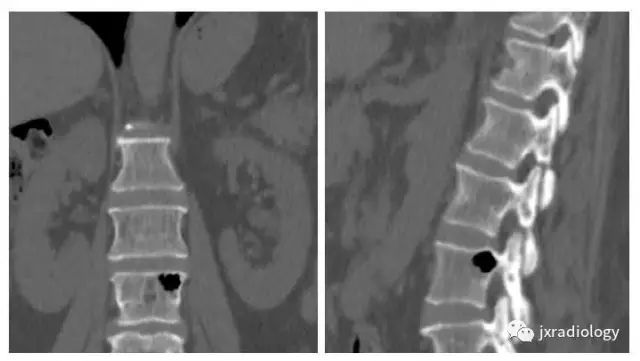

影像资料:

CT:被认为是最好的诊断方法,CT值约-800~-1000HU,椎体及椎间隙内可见气体可以看到相连续的层面,有时会向硬膜外扩张。MRI:气体在T1及T2均为低信号,易和硬化性病变混淆,CT有助于诊断。随访发现一些病灶会增大,但不需要特别治疗。